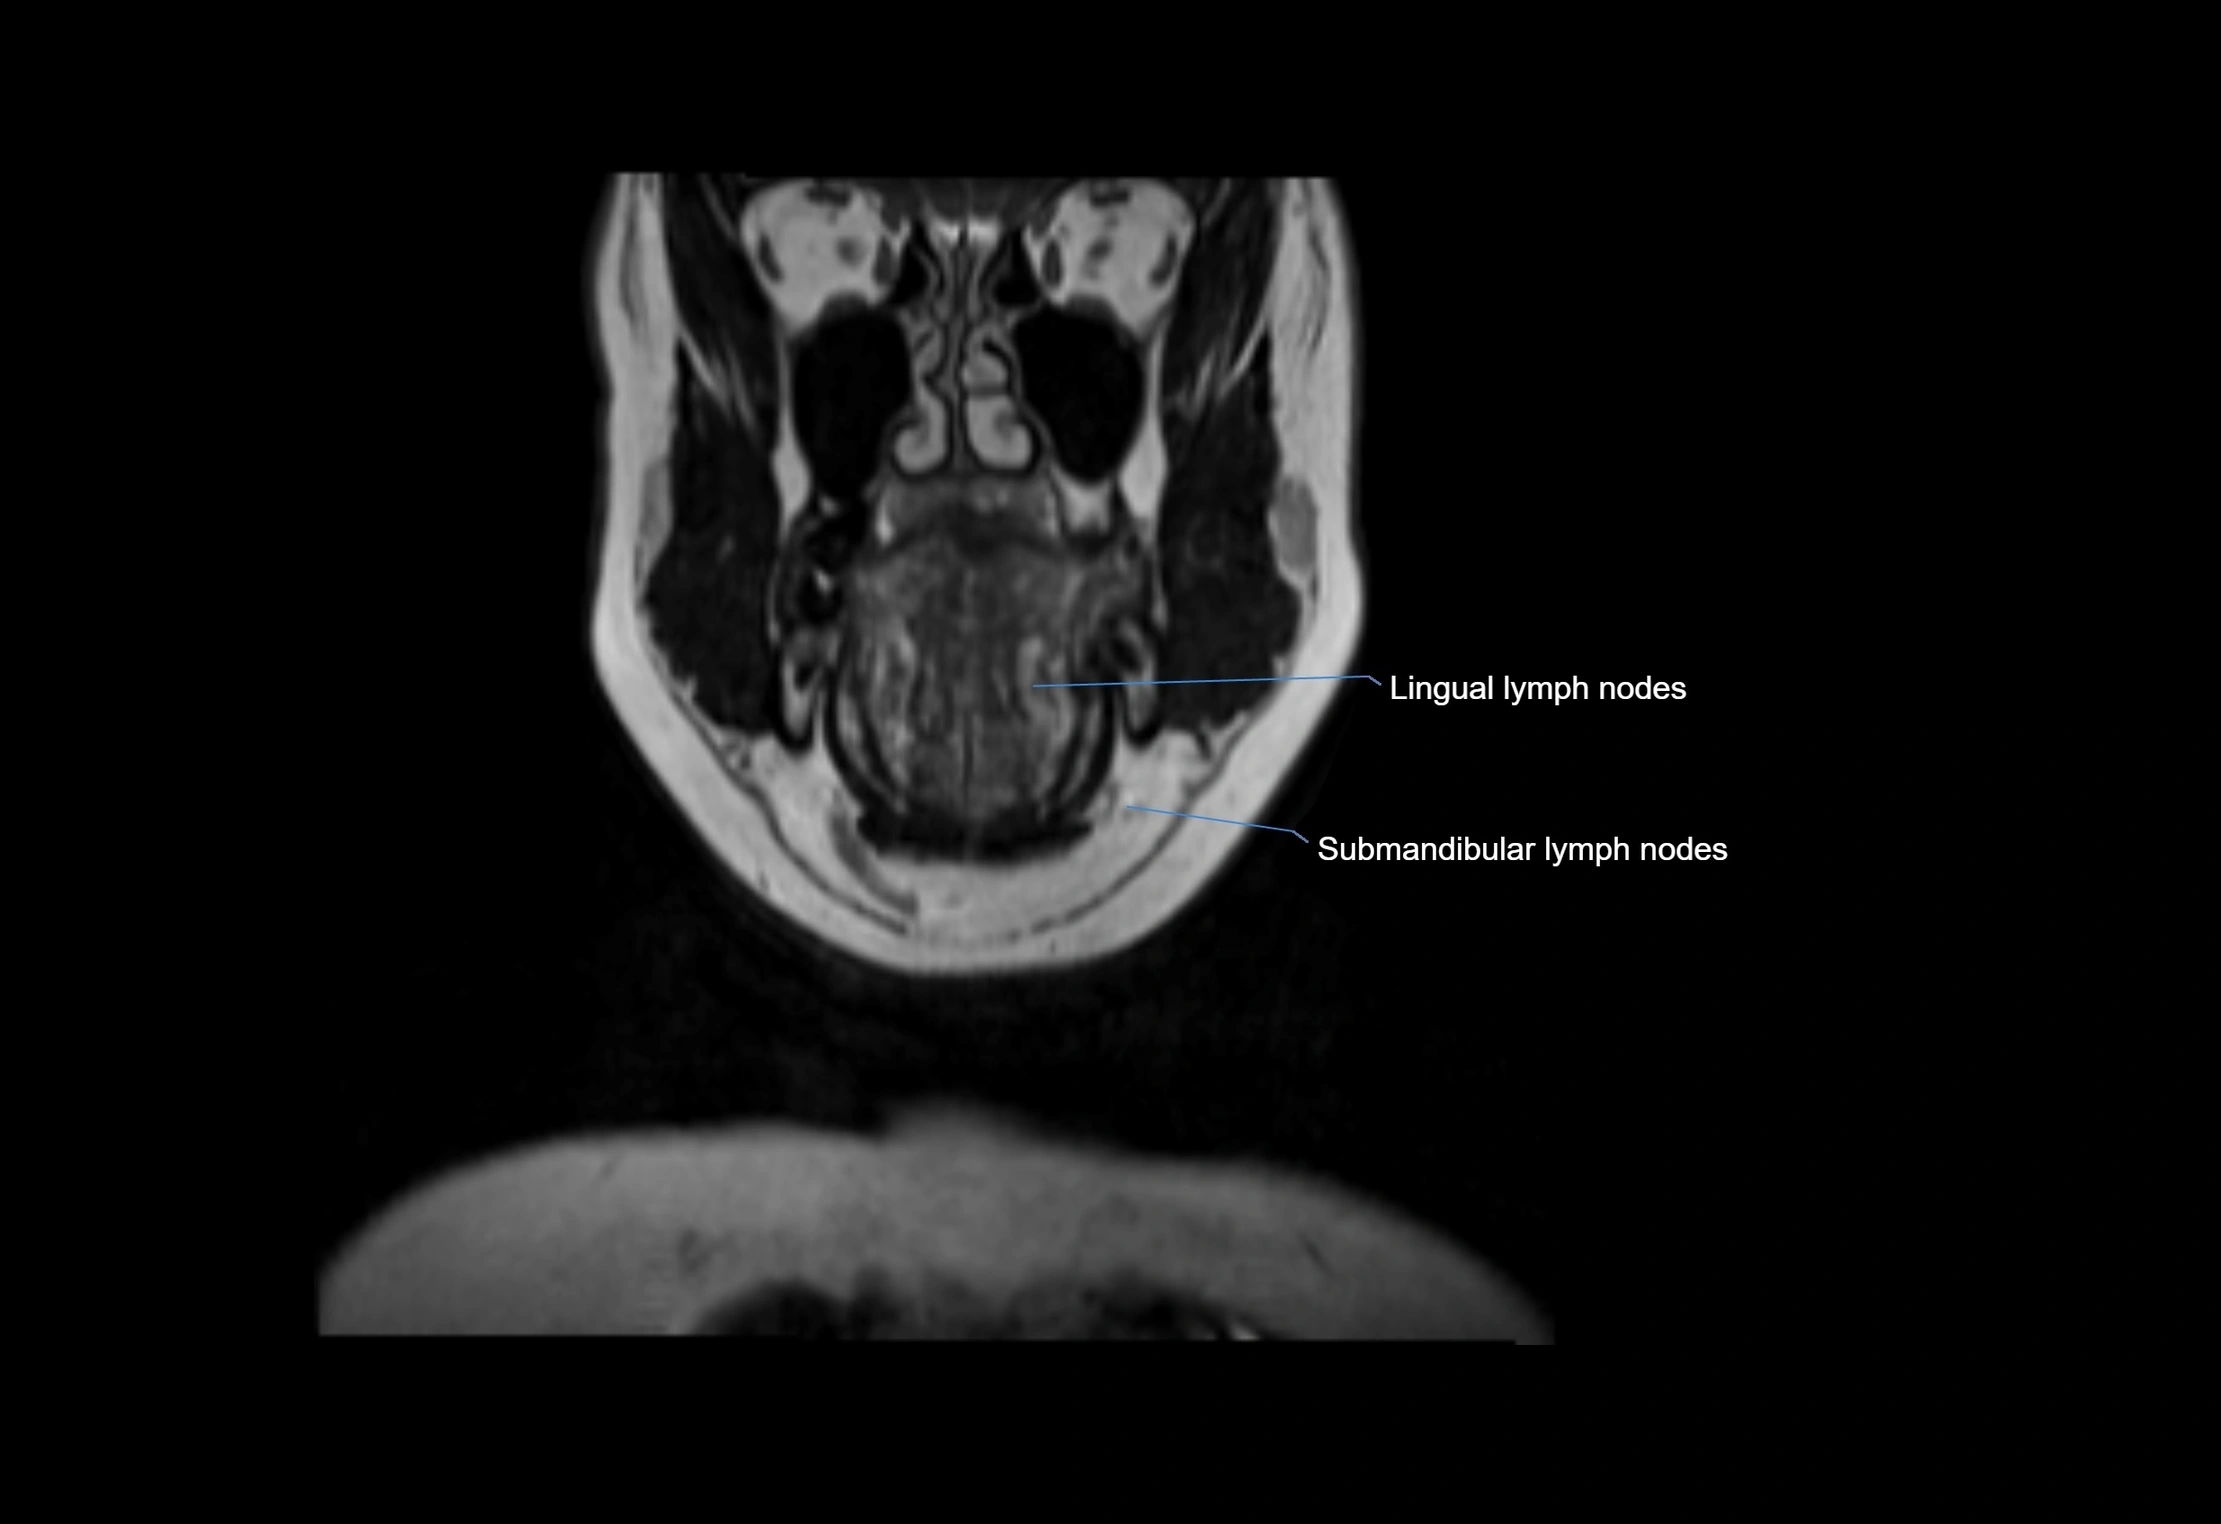

MRI images

image